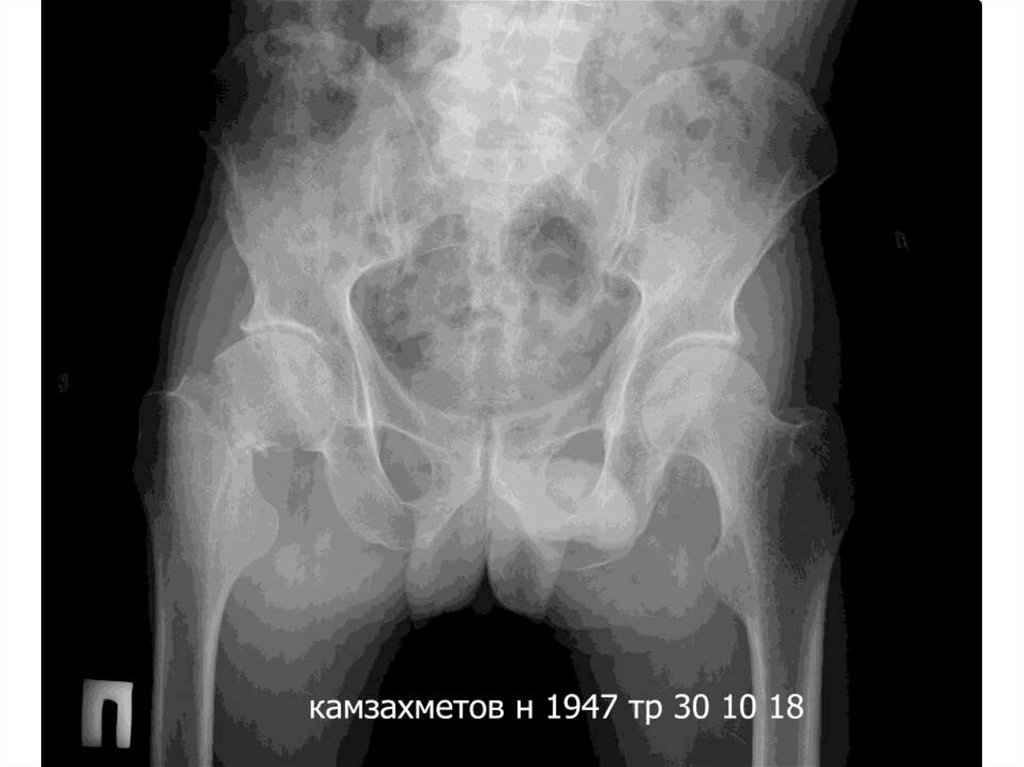

9. КАМЗАХМЕТОВ НУРЛАН     12.06.1947 (71 жас)

КАМЗАХМЕТОВ

НУРЛАН 12.06.1947

(71 жас)

Диагноз:Оң жақ ортан жілік сүйек мойынының

жабық сынығы.

Операция: Оң жақ жанбас-сан буының тотальді

эндопротездеу.